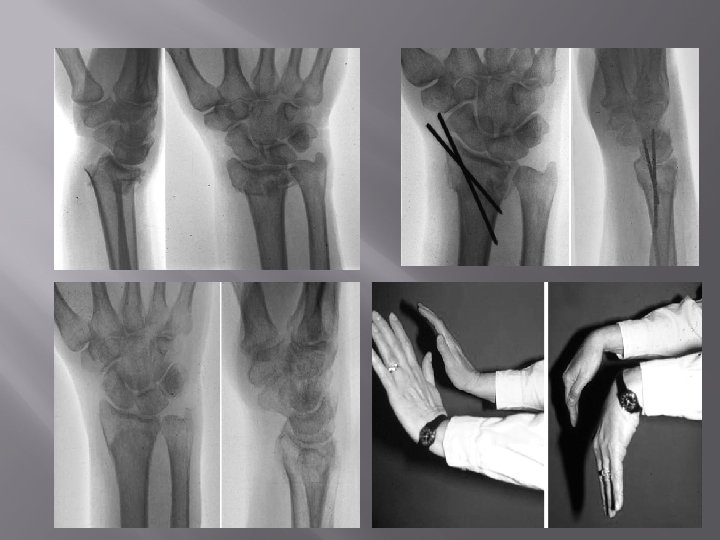

COLLE'S FRACTURE/ POUTTEAU'S FRACTURE � Definition: Fracture of distal metaphysis of radius within 2 cm of the articular surface, may extend into distal radiocarpal or distal radioulnar joint, commonly occurring in elderly females due to fall on outstretched hand – fracture occurs when dorsiflexion varies from 40 o to 90 o. Clinical Features: Pain, swelling. Deformity – Dinner fork deformity / silver fork deformity / spoon shaped deformity [due to dorsal tilt or rotation]. Sign: Tenderness present over lower end radius. Crepitus � Abnormal mobility � � Present but not tested due to pain

� � Styloid Process Test: Both styloid present at same level in Colle's [Normal radial styloid 1. 3 cm lower than ulnar]. Radiology: X-ray wrist – AP Lateral Treatment Conservative a) Colle's cast : Below elbow cast with 10 -20 o palmar flexion, 15 o-20 o ulnar deviation. b) Above elbow cast in midpronation is BEST. Cast is usually given for 6 weeks. Surgical � Closed reduction and percutaneous K-wire fixation. � Open reduction and fixation using plates and screws � External fixation [for compound fractures and fractures with extensive communition].